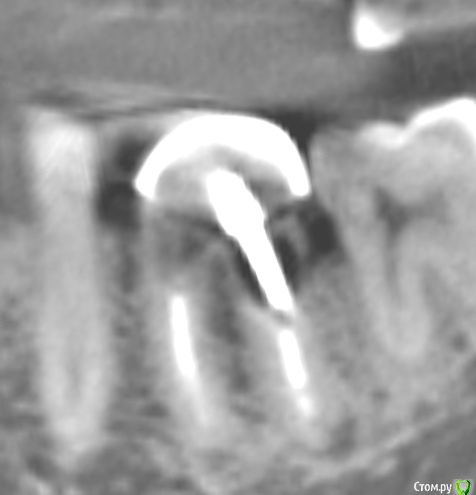

krokomot Опубликовано 26 февраля, 2015 Поделиться Опубликовано 26 февраля, 2015 Уважаемые коллеги есть сомнительный зуб который 10 лет разрушался под штампованной коронкой. Предложите варианты лечения, не учитывая эндодонтическое лечение. И стоит ли?! Всем спасибо за участие. после некрэктомии Щадящей! Ссылка на комментарий

krokomot Опубликовано 26 февраля, 2015 Автор Поделиться Опубликовано 26 февраля, 2015 Тем неменее перфорций стенок нет, полноценная только вестибулярная стенка разделения корней нет, устойчив. не беспокоил. Удалить проблем нет, как вы думаете возможно ли восстановление, если можно обосновывайте ответ. Хотел еще фото с внутри ротовой но ассистент удалил Ссылка на комментарий

chervoncevdaniil Опубликовано 26 февраля, 2015 Поделиться Опубликовано 26 февраля, 2015 Тем неменее перфорций стенок нет, полноценная только вестибулярная стенка разделения корней нет, устойчив. не беспокоил. Удалить проблем нет, как вы думаете возможно ли восстановление, если можно обосновывайте ответ. Хотел еще фото с внутри ротовой но ассистент удалил Док,дефект ниже уровня кости,очень тонкие стенки,некачественное эндо,феррула тут и в помине нет,какие еще аргументы нужны?целесообразность сохранения такого зуба какая? 2 Ссылка на комментарий

krokomot Опубликовано 26 февраля, 2015 Автор Поделиться Опубликовано 26 февраля, 2015 (изменено) Док,дефект ниже уровня кости,очень тонкие стенки,некачественное эндо,феррула тут и в помине нет,какие еще аргументы нужны?целесообразность сохранения такого зуба какая?Спасибо за поддержку) Просто у пациента как низуб так сюрприз, везде где было эндо все оч плохо кстати в моем посте про каналонаполнители в 3-х каналах тоже его зуб. Изменено 26 февраля, 2015 пользователем krokomot 2 Ссылка на комментарий

krokomot Опубликовано 27 февраля, 2015 Автор Поделиться Опубликовано 27 февраля, 2015 Удаляйте лучше. Зачем вам проблемы с этим пациентом в будущем?Обновлено. Добавляю недостающее фото удалил после повторной ревизии обнаружилась перфа на дистальной стенке, ниже уровня устья. 1 Ссылка на комментарий